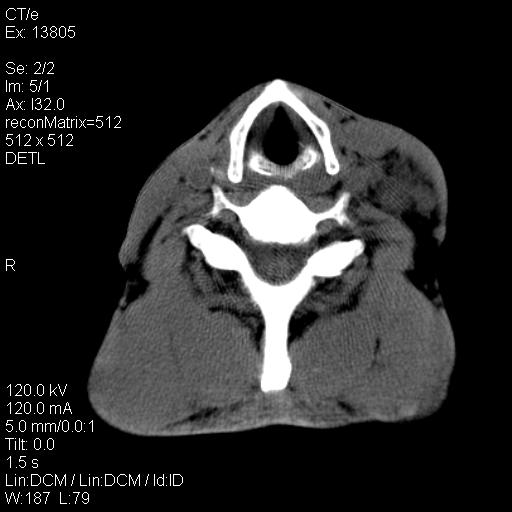

上腹部疼痛一月,呕吐10天,发现左侧颈部包快10天 胸部cr片未见明显异常。

左侧胸锁乳突肌下方、颈血管旁低密度肿块影,肿块密度尚均匀,边缘大部分清楚,邻近组织稍受压移位。考虑颈部神经鞘瘤可能性大。